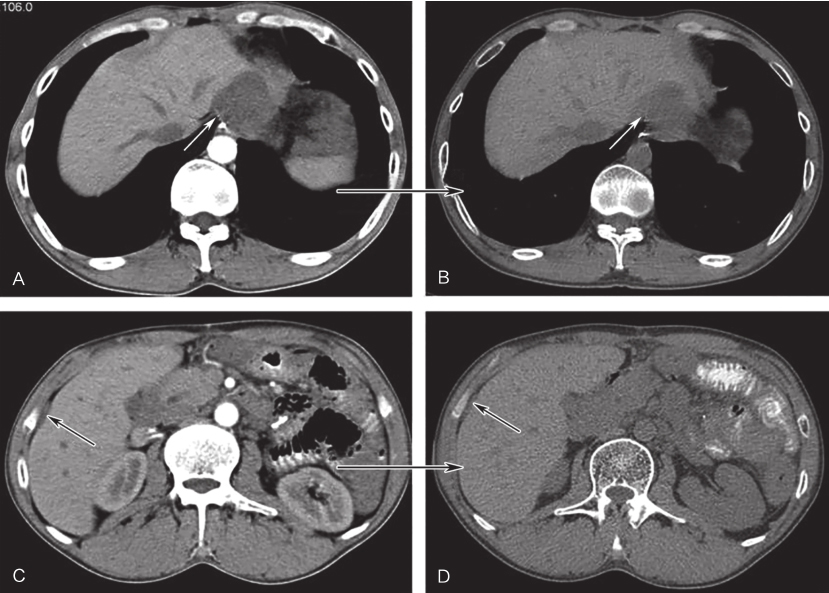

联合用药治疗3个月后,复查CT示吻合口病灶4.6cm×3.9cm,治疗后6个月CT示吻合口病灶3.8cm×3.0cm,肝被膜下及腹腔内病灶与前相仿,未见新发病灶(图6)。联合用药治疗后14个月及19个月CT示:吻合口病灶4.4cm×3.3cm,5.2cm×4.9cm(PD)。

图6伊马替尼联合舒尼替尼治疗6个月后CT增强表现

A、C.治疗前病灶;B、D.治疗6个月后病灶;白色箭头示吻合复发病灶,黑色箭头示肝包膜转移灶